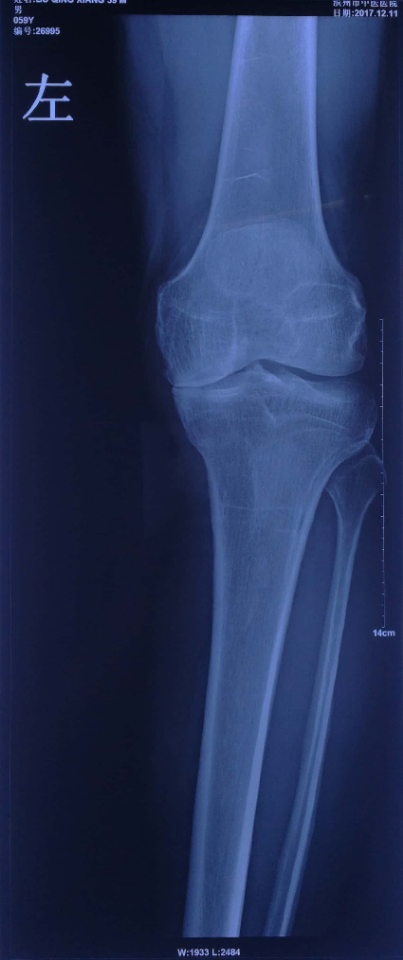

术前负重位X线片显示:患者膝内翻畸形,膝关节内侧间隙消失